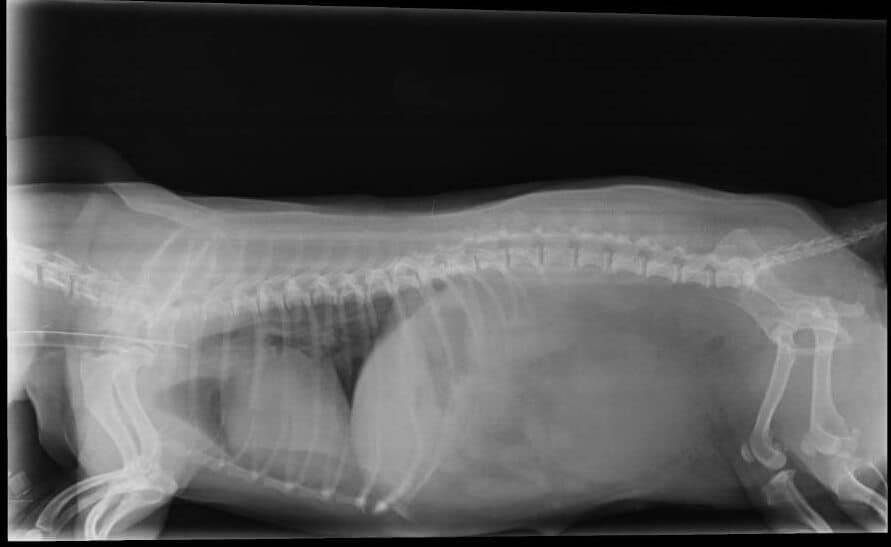

Диагностика и лечение собаки с пупочной грыжей

УЗИрентген

Лечение пупочной грыжи только хирургическое. Часто эту операцию совмещают с удалением яичников и матки у сук. Во время операции под общей анестезией содержимое грыжевого мешка смещается в брюшную полость, грыжевой мешок иссекается, грыжевые ворота (пупочное кольцо) ушивается.

Лечение ущемленной грыжи гораздо сложнее, и часто требует удаления части кишечника, так как при ущемлении он быстро некротизируется (отмирает), некротизированные участки обязательно удалять. Поэтому грыжу рекомендуется удалять у собаки в молодом возрасте, до того, как она начнет угрожать здоровью собаки. Чем более своевременным будет обращение, тем более благоприятный прогноз на восстановление будет после операции. При небольшой грыже, без ущемлений, хирургическое вмешательство проводится достаточно быстро, вероятность осложений минимальна

Если уже произошло ущемление, все будет зависеть от того, насколько серьезно успели некротизироваться органы, если уже начался перитонит – прогноз от осторожного к неблагоприятному.